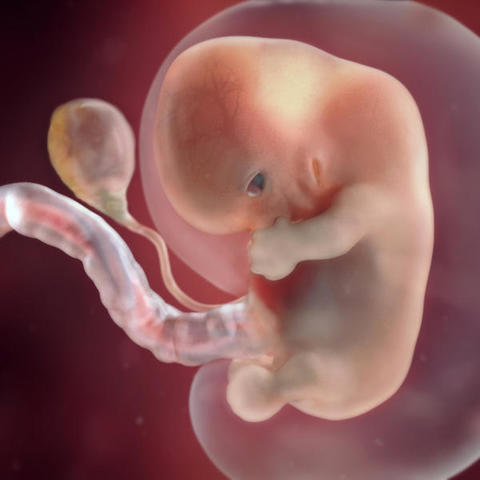

• Semana 9 - Inicia el periodo fetal

Semana 9 - Inicia el periodo fetal

Mide entre 17 y 22 milímetros. Y físicamente también ha cambiado mucho: la cola ha desaparecido y la cabeza se ha separado un poco del cuerpo gracias a un incipiente cuello que humaniza su silueta.

- Los ojos se acercan entre sí, mientras que los párpados empiezan a formarse y casi cubren los ojos. Ya ha aparecido el labio.

- Se forman los pezones y los folículos pilosos.

- Los brazos crecen y se desarrollan los codos.

- Se pueden observar los dedos del pie del bebé.